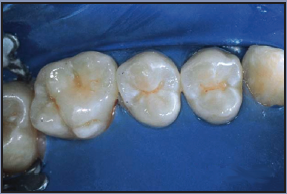

The occlusal surfaces of first and second permanent molars are regarded as the teeth most susceptible to caries, and therefore the teeth likely to benefit most from sealants. However, any teeth assessed at risk can benefit from sealant application. Recent studies suggest that sealants can be placed effectively on buccal and lingual surfaces in pits and along deeper developmental grooves. Adding an intermediate layer of bonding agent primer and adhesive is more advantageous on these surfaces than on occlusal surfaces.

After the rinsing is completed, the tooth must be dried with air that is free of oil and moisture. The specific amount of time to dry is not as important as the specific result. A tooth which has been properly etched, rinsed, and dried will exhibit a white, dull, and frosty appearance. If this frosted appearance does not occur, re-etch the tooth surface, rinse, and dry until the desired appearance of the tooth has been achieved. The procedure should also be repeated if saliva contamination occurs at any time during the application of the etchant.